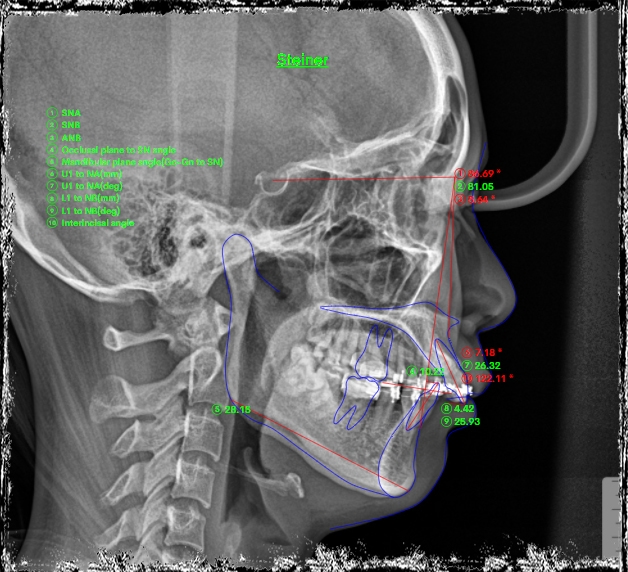

Kết quả phân tích phim: khớp cắn hạng II cả răng và xương, khớp cắn sâu 100%

Tình trạng trục răng lệch, sai nhiều do hiệu ứng cuộn & do gắn mắc cài sai.